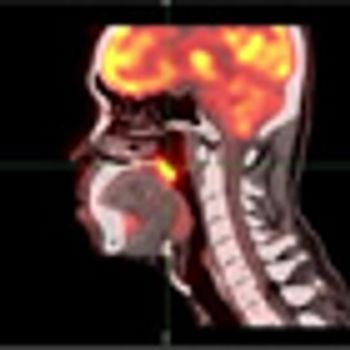

Researchers in China have found that the use of [18F] fluorodeoxyglucose PET/CT detected a greater number of distant metastases than conventional work-up imaging in patients with nasopharyngeal carcinoma.